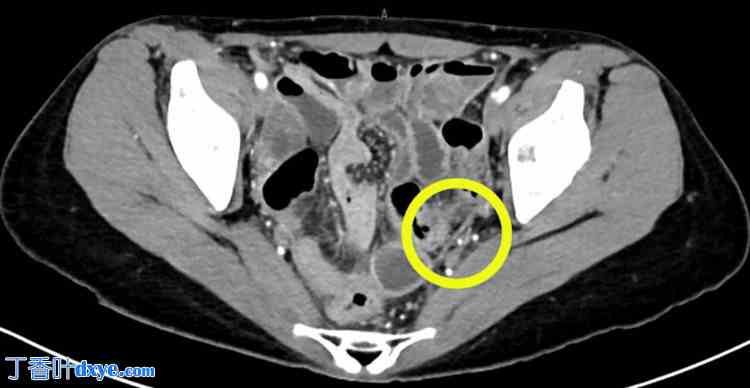

血液检查显示白细胞计数(14,500/μL)和C反应蛋白水平(19.02 mg/dL)显著升高。计算机断层扫描(CT)显示盆腔腹膜轻度增厚,诊断为腹膜炎(图4)。

图4. 盆腔增强CT扫描。